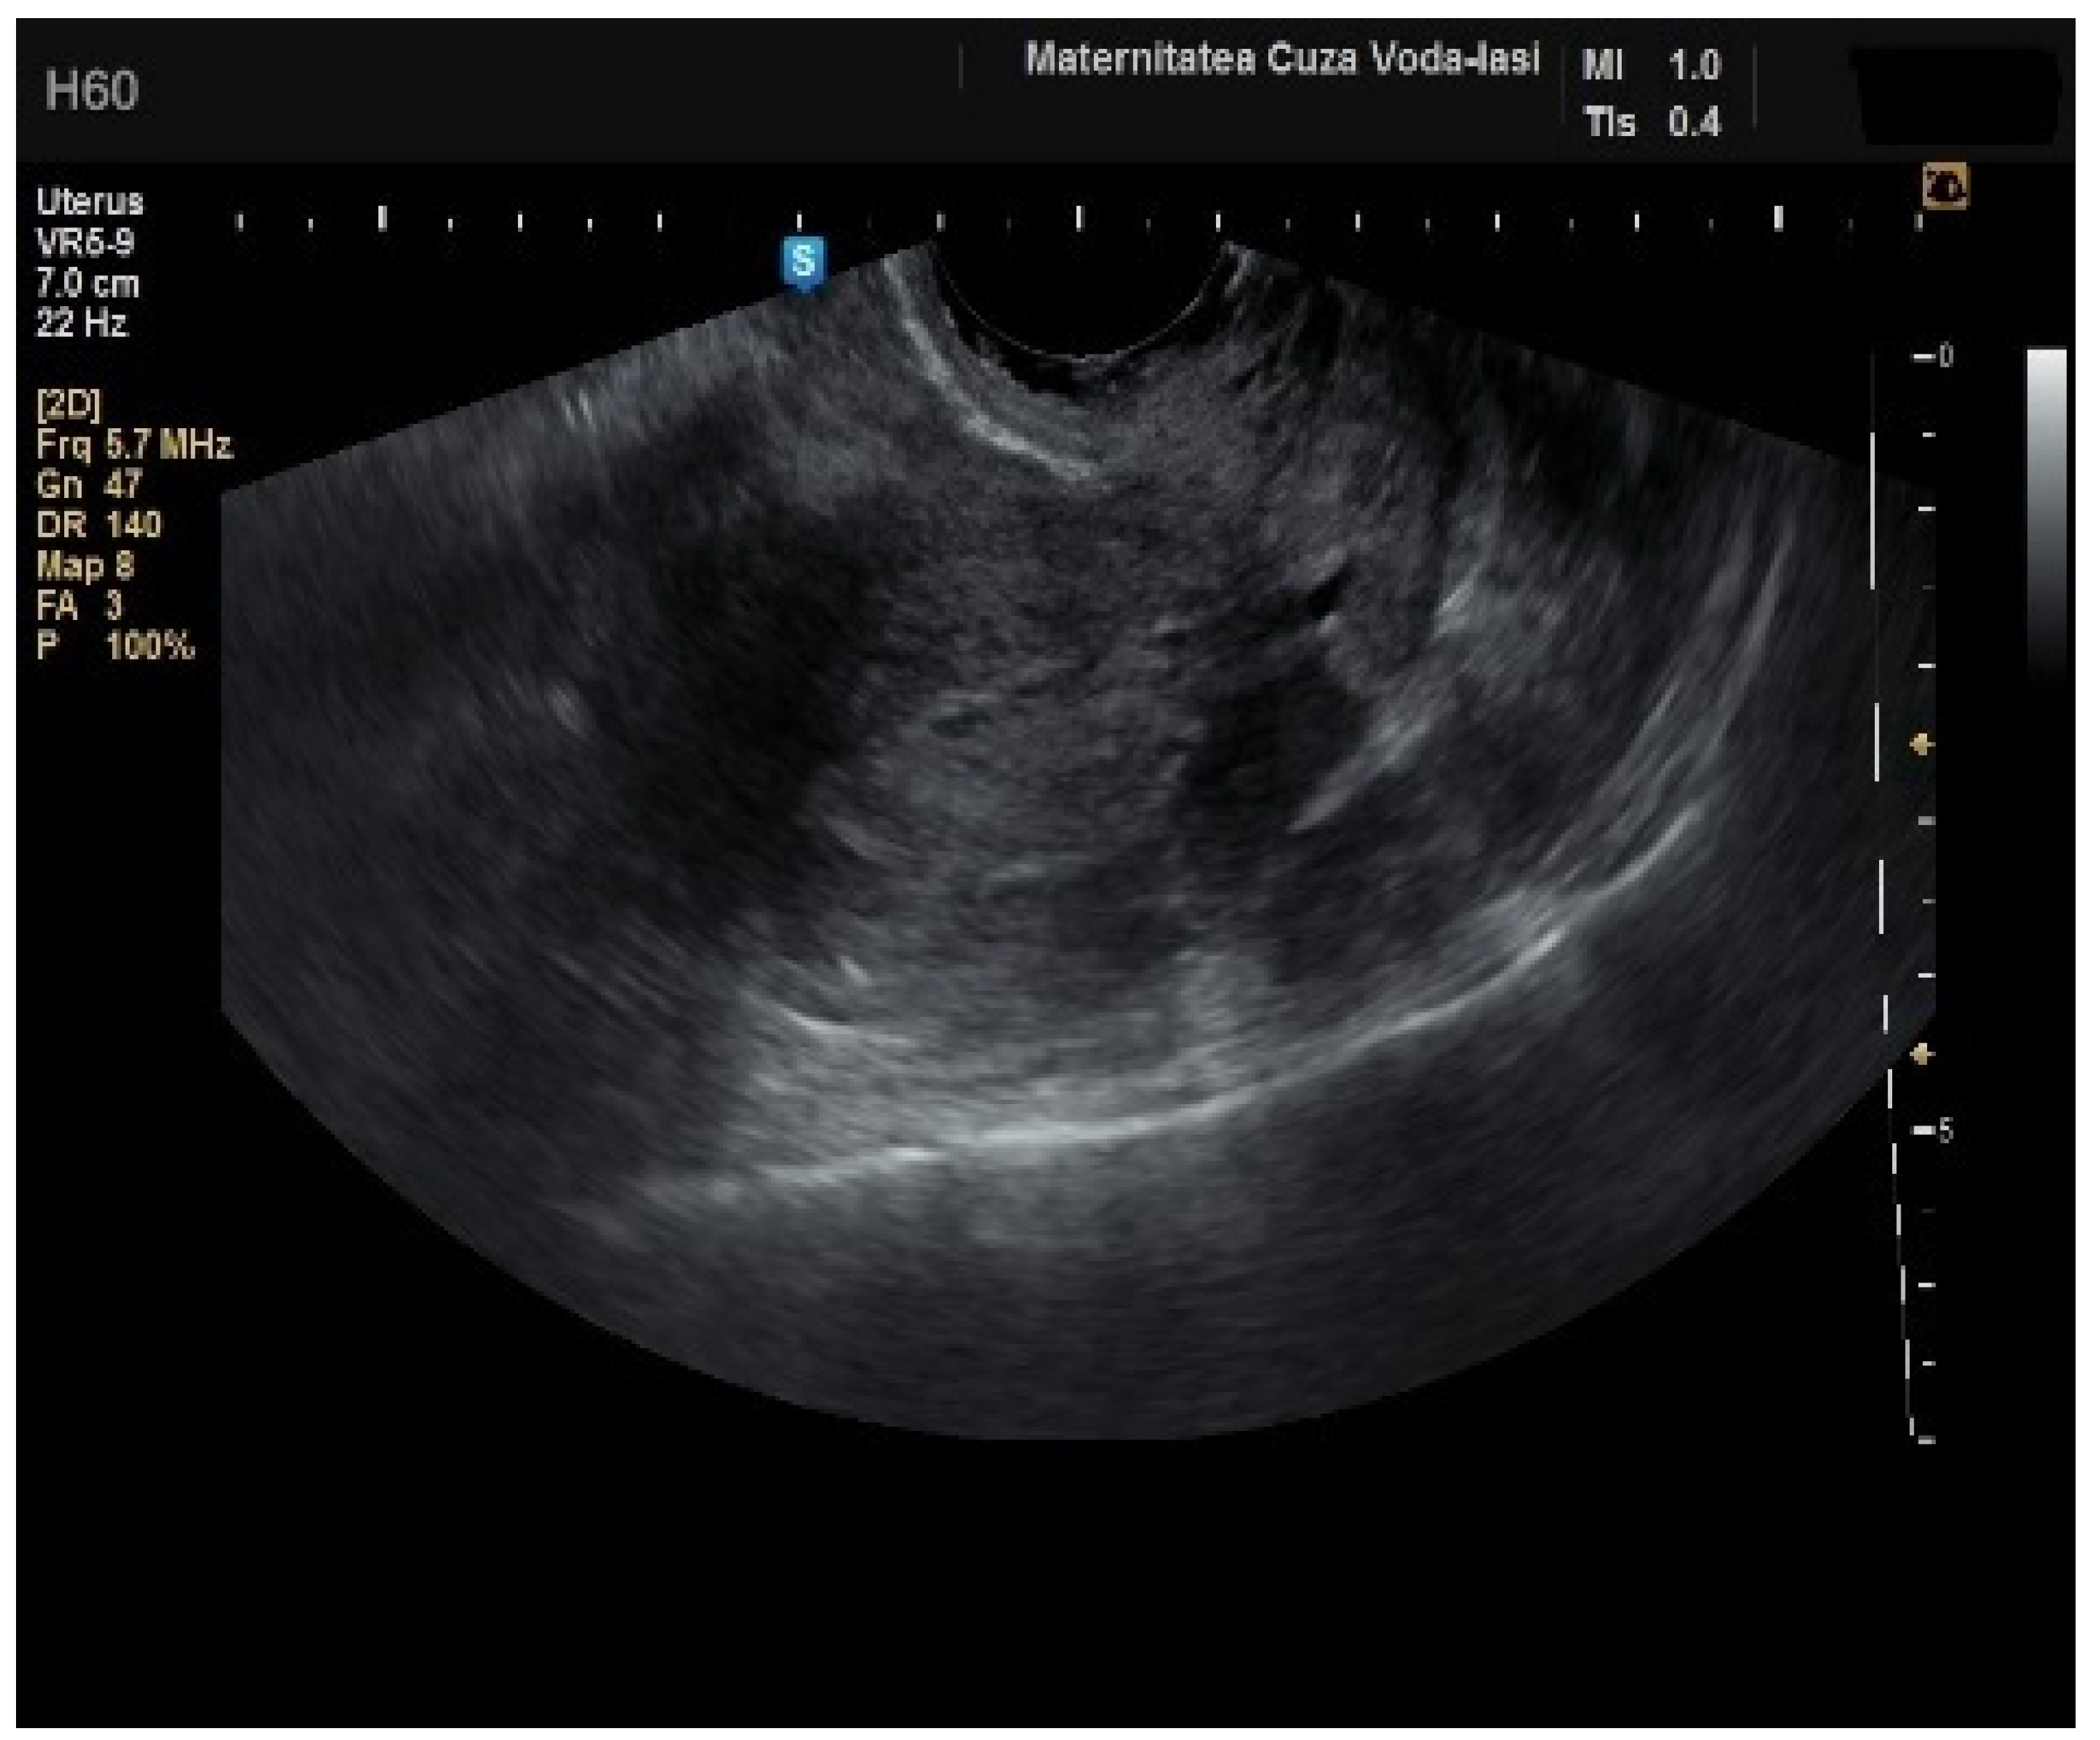

Figure 3. Ultrasonographic imaging of endometrial polyps.

The average endometrial thickness, as measured by transvaginal ultrasonography, was found to be 18.02 ± 10.94 mm (range: 5–64 mm). Malignancy was identified in 22.84% of cases with uterine cavity findings. The mean endometrial thickness for women diagnosed with endometrial cancer was 24.49 ± 13.33 mm (95% confidence interval [CI]: 14.34 to 35.16), (Figure 2), whereas those with other pathologies had a mean thickness of 16.10 ± 9.37 (95% CI: 13.14 to 18.57), (Figure 3), with statistical significance (p = 0.028). When endometrial thickness was used as a standalone variable to build a model for estimating the risk for endometrial malignancy it demonstrated the highest AUC with a value of 0.682 (95% CI: 0.452–0.912). A cut-off threshold of 26 mm for endometrial thickness yielded a sensitivity of 62.5% and a specificity of 89% (Figure 4).

The mean age for patients with endometrial polyps was 50.70 ± 8.40 years (p = 0.001). The average endometrial thickness for the endometrial polyps was 13.68 ± 4.37 mm (p = 0.001), with a threshold value of 9.8 mm, yielding a sensitivity of 0.767, and specificity of 0.23, which lacked predictive value. There was no correlation between the internal structure of the endometrium and its echogenic homogeneity—heterogenous endometrium showed a sensitivity of 90.9% (95% CI: 0.7219 to 0.9747) and specificity of 46.51% (95% CI: 0.3251 to 0.6108) (Figure 15). The endometrial–myometrial junction remained regular in all cases of endometrial polyps. Usually, the vascular score for polyps was 1, with a single dominant vessel penetrating from the myometrium into the endometrium, either with (Figure 16) or without branching (Figure 17), although vascularization was not observed in 68.4% of participants with polyps.